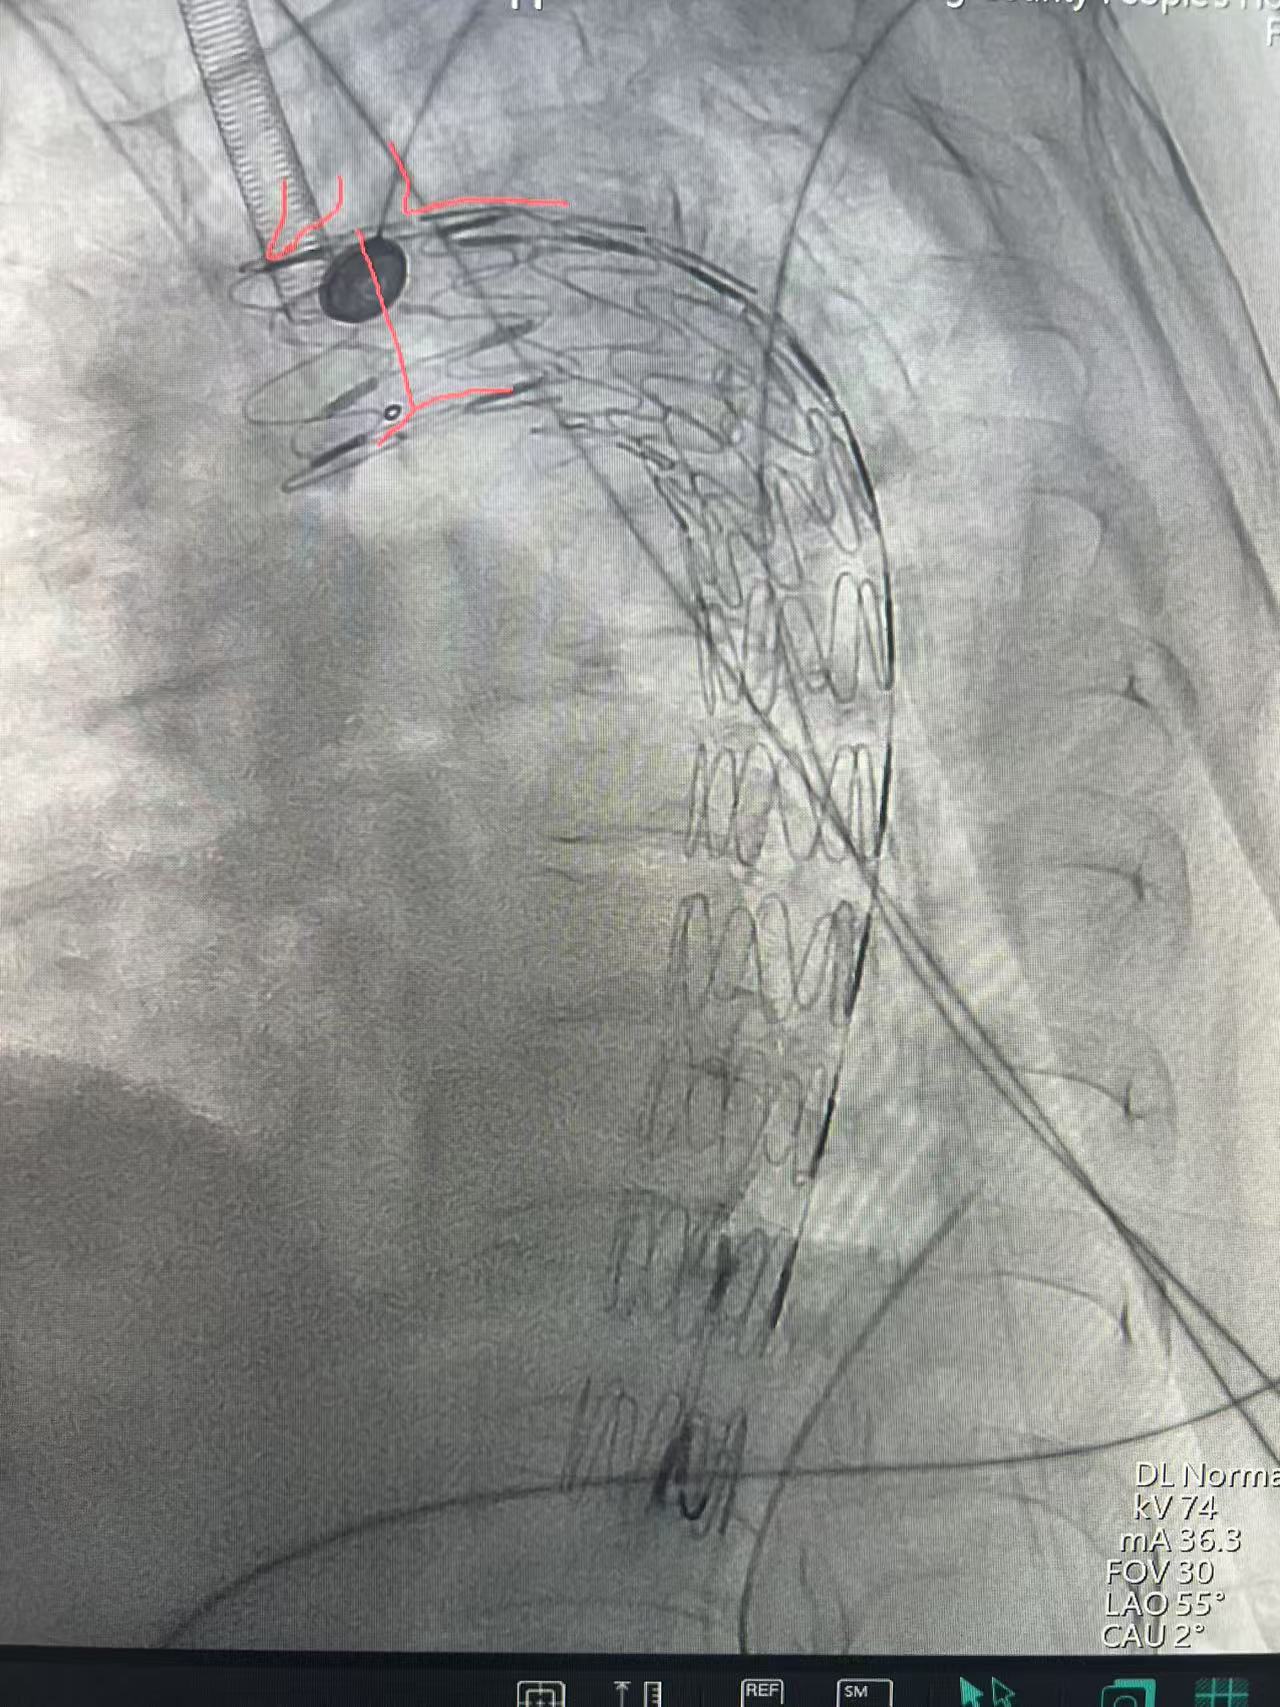

术后

医院重症医学科、胸外科、骨科、医学影像科、麻醉科、介入科等多学科会诊讨论,针对伤情制定合理的治疗方案,在一系列稳定患者血流动力学治疗后,医务科再次针对胸主动脉假性动脉瘤组织多学科会诊。在院外专家指导下为患者实施胸主动脉覆膜支架腔内隔绝的介入手术,手术在数字减影血管造影(DSA)设备的精准引导下,通过患者两侧大腿根部穿刺股动脉,将覆膜支架经血管输送至胸主动脉损伤部位,成功隔绝血管破裂口,有效阻止了破口进一步撕裂。整个手术过程紧张有序,仅耗时40分钟便顺利完成,术中患者生命体征平稳,术后被安全送回重症病房观察。